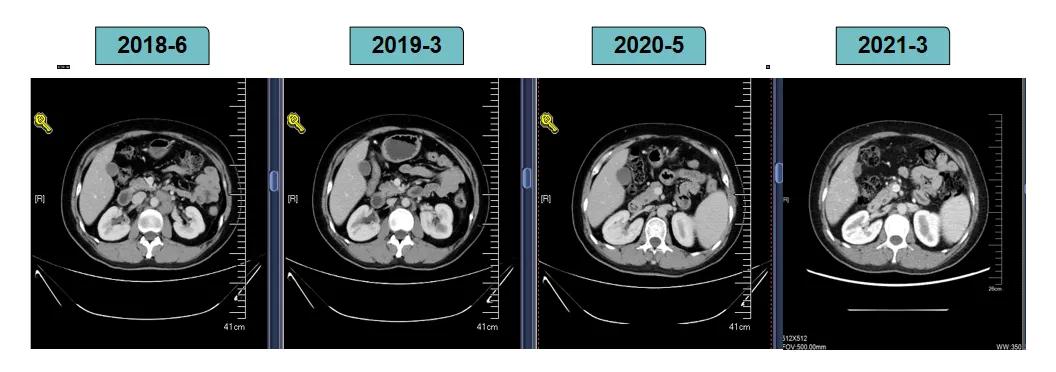

靶病灶:腹主动脉左侧和下腔静脉右侧淋巴结

非靶病灶:肝左叶、肝右前叶下段;纵膈胸骨后淋巴结节;前上纵膈淋巴结;腹膜后小淋巴结

影像学评估-腹膜后淋巴结: